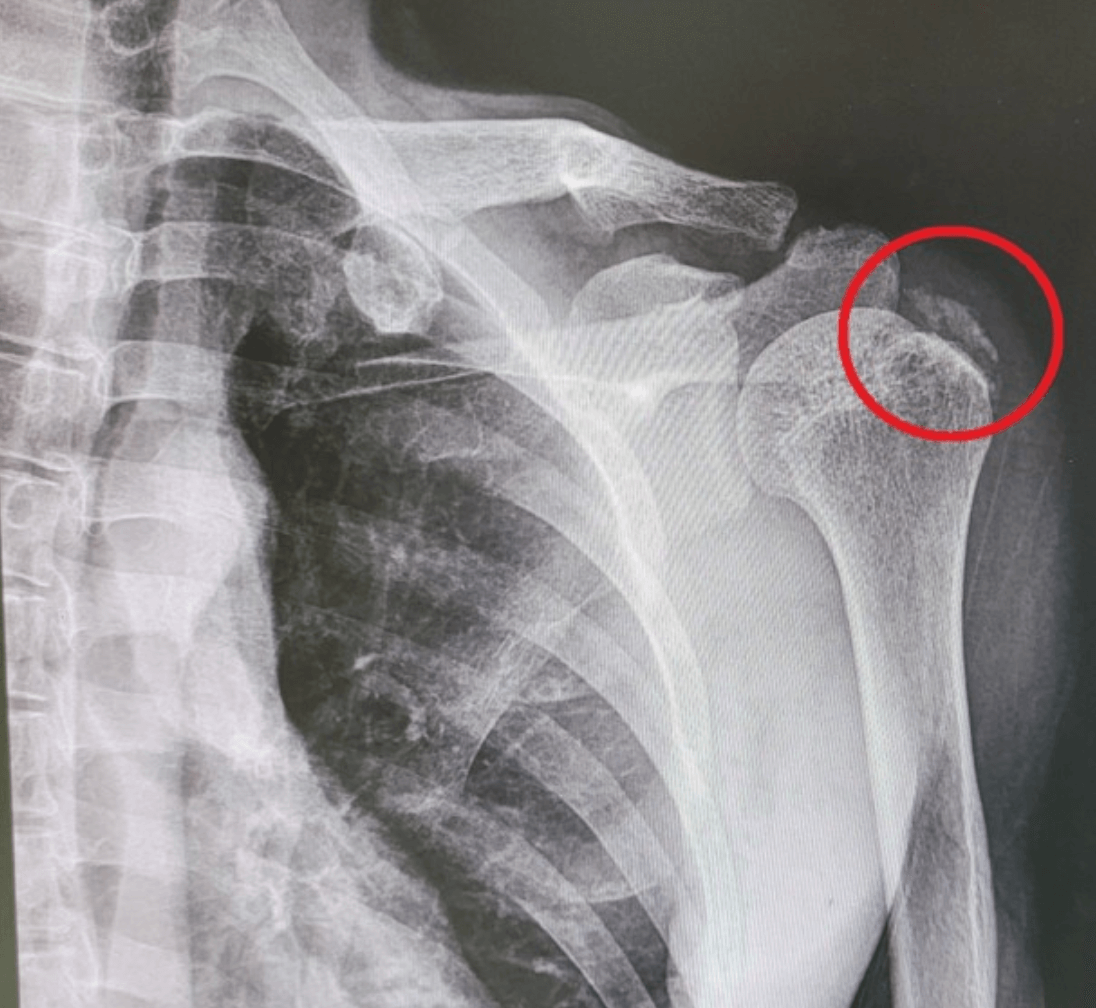

어깨 석회성 건염은 어깨 힘줄에 석회가 침착되어 발생하는 질환입니다. 견봉하근(rotator cuff)이라고 불리는 4개의 힘줄 중 하나에 영향을 미치는 경우가 많습니다. 어깨 석회성 건염은 주로 40세 이상의 남성에게서 많이 발생하는데요. 이번 글에서는 어깨 석회질치료방법 및 주요 증상, 원인과 예방법에 대해 알아보겠습니다.

어깨 석회성 건염의 주요 증상은 어깨 통증으로, 경증부터 중증까지 다양하며 특정 움직임이나 활동에 따라 악화될 수 있습니다.

특히 팔을 위로 들어올리거나 뒤로 돌리는 것이 어려울 수 있습니다. 이러한 통증은 야간에 더 심해지며, 석회질이 생긴 힘줄에 부종이 생겨 부어오를 수 있습니다. 석회화 정도 및 칼슘 침전물의 크기에 따라 증상이 달라질 수 있으며, 간혹 팔에 힘이 잘 들어가지 않는 증상이 나타나기도 합니다.